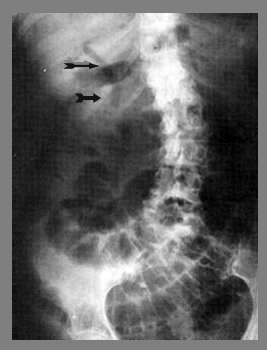

בצילום בטן סקירה ניתן לראות חסימות דינמיות, התרחבות של המעי הדק (תצלום 1.4), ופלסי אוויר נוזל במרכז הבטן המסודרים בצורת מדרגות (תצלום 2.4). הוולבולה קוניובנטס מודגשים לרוחב הרירית (תצלום 3.4).